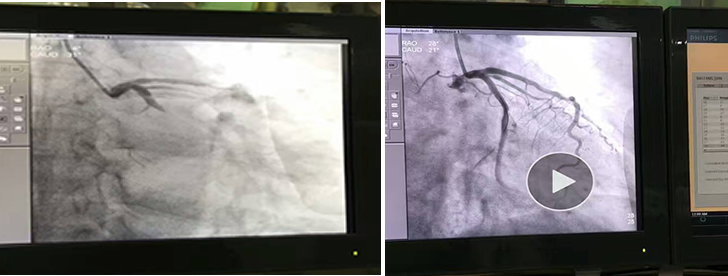

?6月19日,心內(nèi)科又迎來繁忙的一天,心內(nèi)導管室從早上8點開始,就投入緊張的手術(shù)之中,連續(xù)11臺介入手術(shù),一直進行到晚上九點多。背負著沉重的鉛衣,參加手術(shù)的每個人都已經(jīng)疲憊不堪,在他們剛剛回到家還沒來得及休息,一個急診電話響起,不到二十分鐘,大家又迅速的集合在急診手術(shù)室的臺前,為一位63歲的急性下壁心肌梗死的男性患者實施急診手術(shù),患者CAG顯示:患者左回旋支血管100%急性閉塞。術(shù)中再灌注性心律失常發(fā)生,生命體征極不穩(wěn)定,心率40次/分,血壓80/50mmHg,在徐曉輝主任、宋宜生副主任、張龍醫(yī)生的嫻熟操作以及郭紀文、于永利護士的全力配合下,患者閉塞的血管被開通,并成功植入2枚支架。術(shù)后患者生命體征漸平穩(wěn),胸悶、胸痛癥狀明顯減輕,這時已接近凌晨一點鐘。